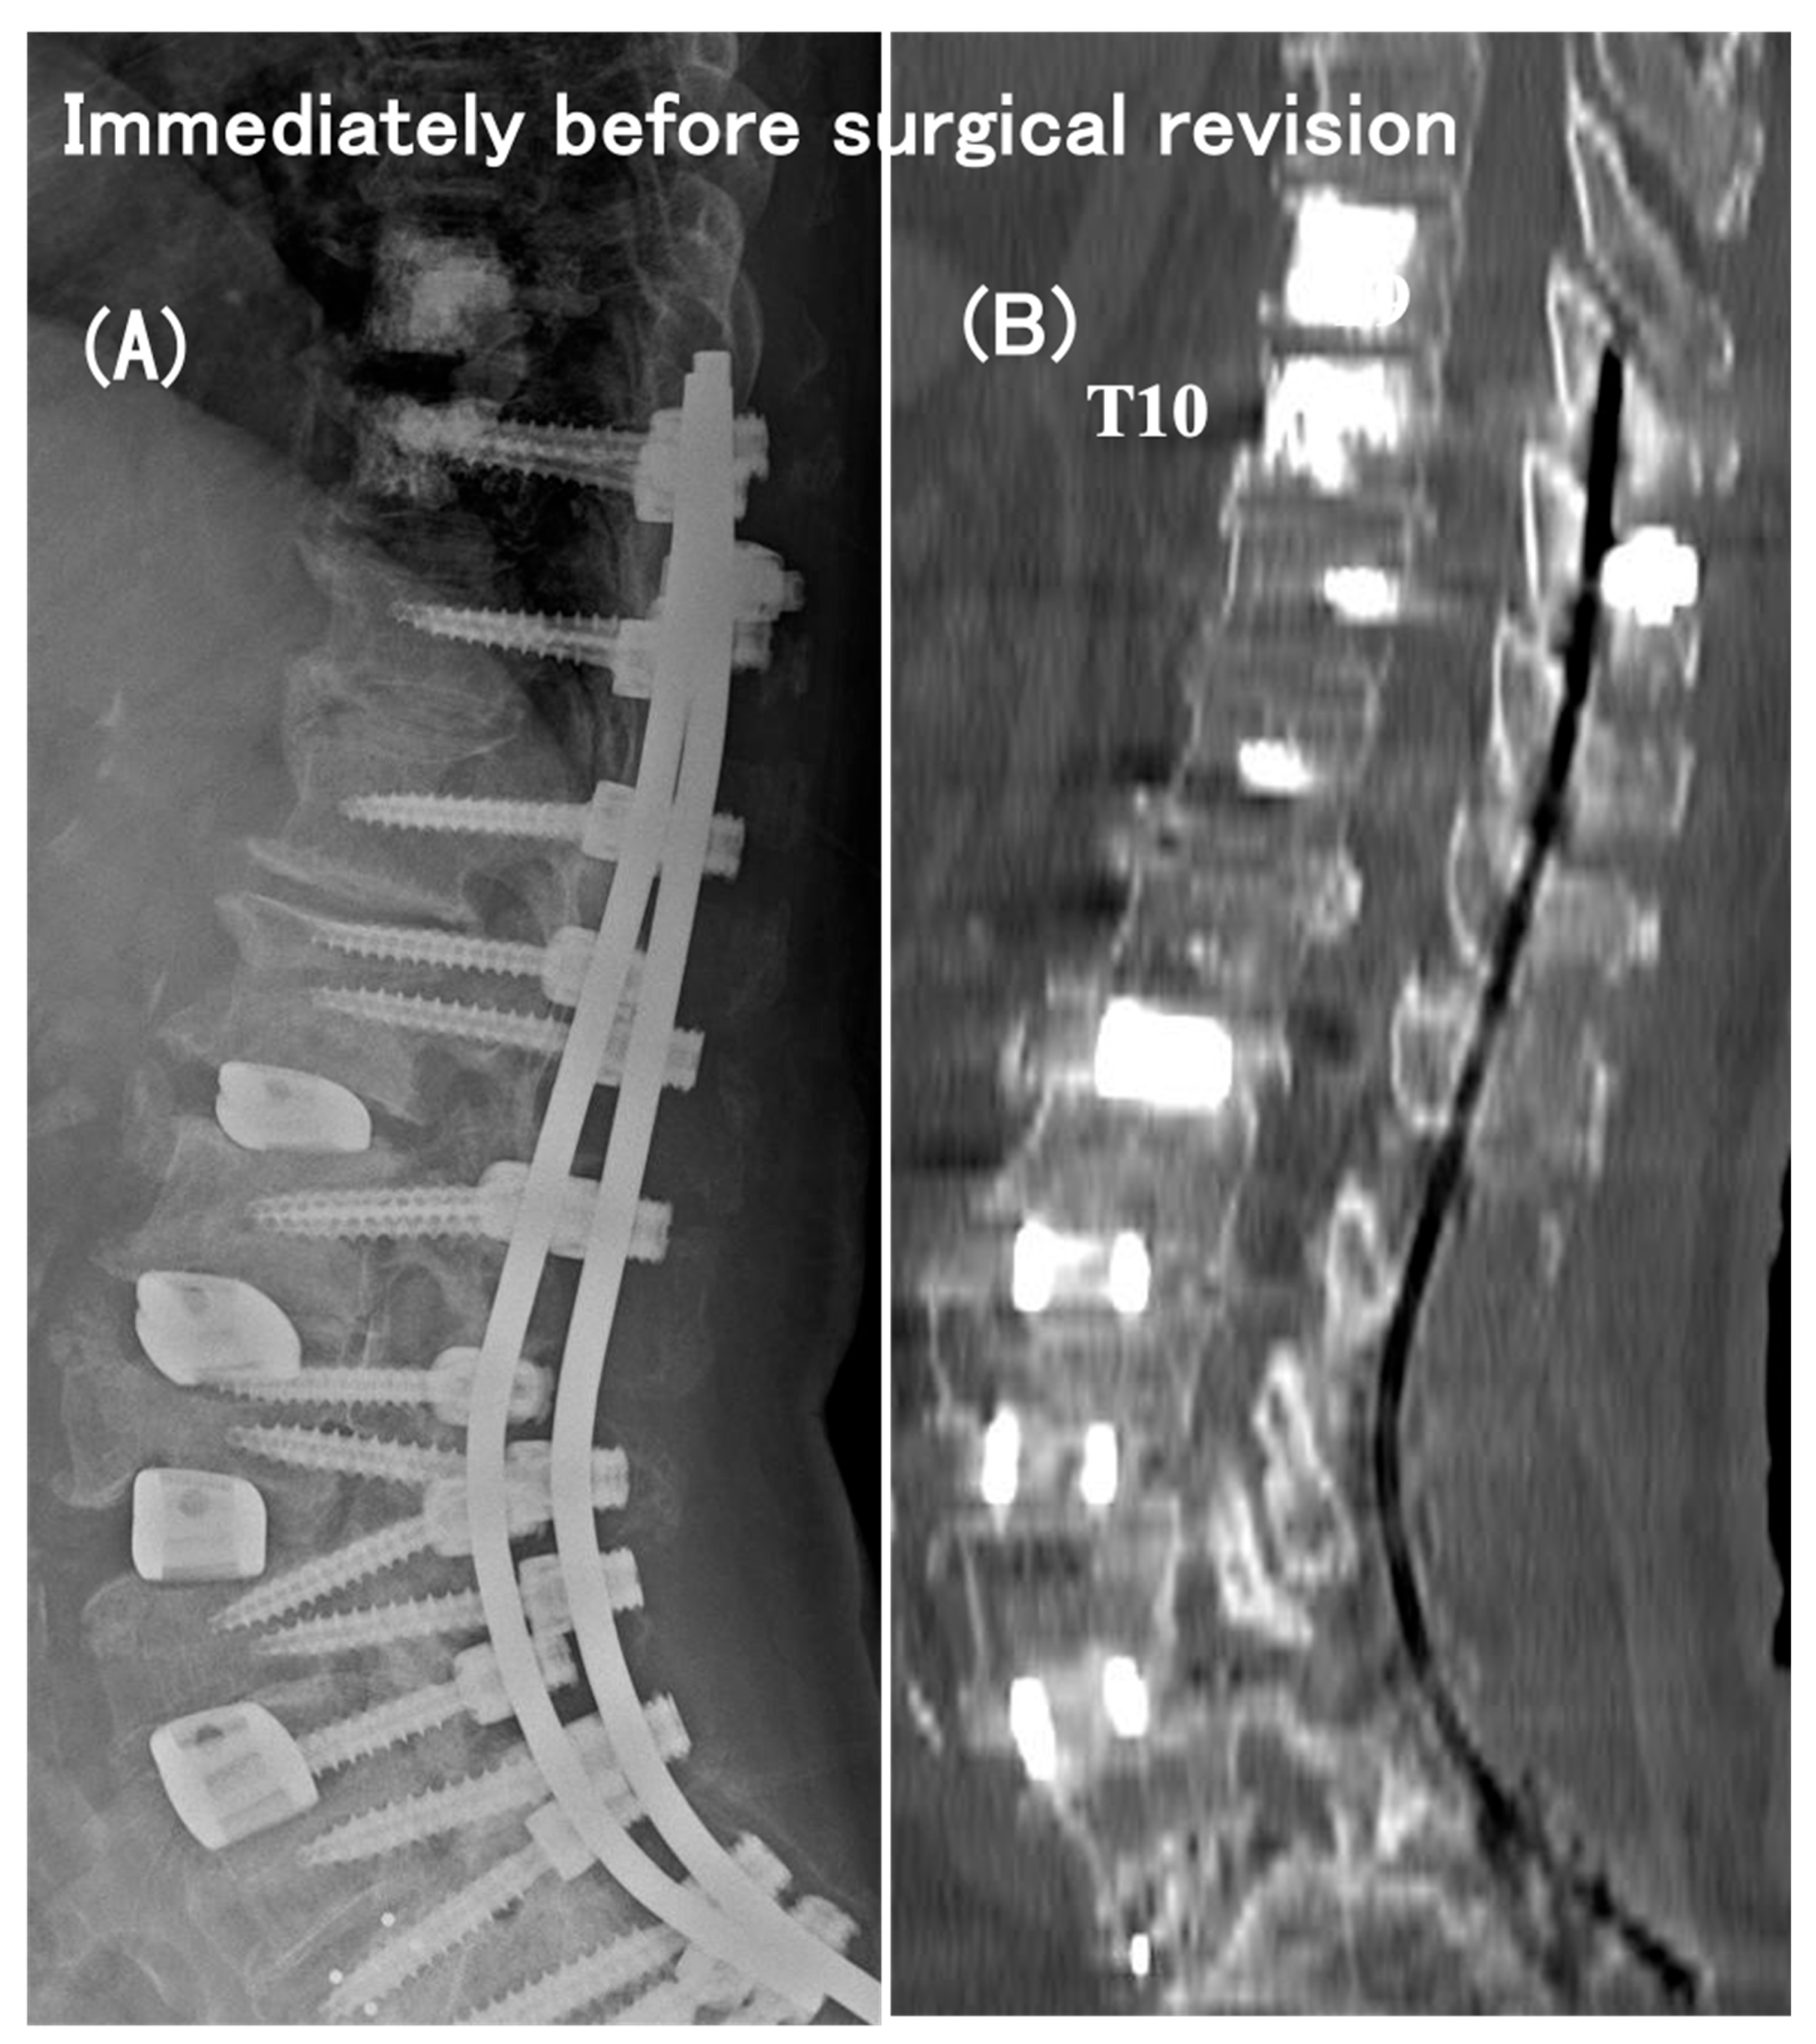

3.6. Case Presentation

- Case no. 6

- 2.

- Case no. 4

| Case No. | Modified Frankel Grade § | Vertebral Collapse | Segmental Instability | Time Interval Between the Initial Op and PJF (month) | Proximal Extension of Fusion | Decompression | Modified Frankel Grade | FU (months) | |||||||||

| 1 | D3 | T8, T10 | – | 13 | T5 | − | D3 | 79 | |||||||||

| 2 | D1 | T10 | UIV–UIV + 1 | 20 | T5 | - | D3 | 37 | |||||||||

| 3 | C | T9, T10 | UIV–UIV + 1 | 4 | T3 | + | D2 | 77 | |||||||||

| 4 | D1 | T10 | UIV–UIV + 1 | 6 | T5 | + | D2 | 40 | |||||||||

| 5 | C | T9 | UIV–UIV + 1 | 14 | T5 | + | D3 | 74 | |||||||||

| 6 | C | – | UIV–UIV + 1 | 2 | T5 | + | D2 | 96 | |||||||||